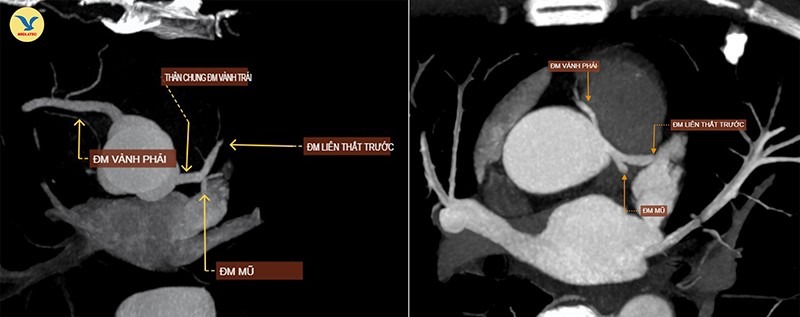

| Hình ảnh chụp CTA. Ảnh trái: Một người bình thường, hai nhánh động mạch vành xuất phát từ hai gốc riêng biệt. Ảnh phải: Hai nhánh động mạch vành của bệnh nhân xuất phát chung một gốc |

Kết quả chụp CTA cho thấy, bệnh nhân mắc một bất thường bẩm sinh hiếm gặp là động mạch vành đơn (Single Coronary Artery), type LII-B. Dị tật này khiến cả hai nhánh động mạch vành trái và phải xuất phát chung từ một gốc duy nhất thay vì hai gốc riêng biệt.

Đáng chú ý, nhánh động mạch vành phải của ông T. đi theo hướng bất thường, bị kẹp giữa thân động mạch phổi và động mạch chủ, gây hẹp bẩm sinh khoảng 45% đường kính. Đây chính là nguyên nhân khiến ông bị đau ngực khi gắng sức, dấu hiệu cảnh báo thiếu máu cơ tim.

Bình thường, tim có hai động mạch vành trái và phải xuất phát từ hai vị trí riêng biệt trên xoang vành của động mạch chủ, dẫn máu nuôi cơ tim. Nhưng ở người mắc dị tật này, chỉ có một gốc động mạch vành xuất phát từ một vị trí duy nhất rồi tỏa nhánh đi nuôi toàn bộ tim.

Type LII-B, phân loại theo hệ thống Lipton, được xếp vào nhóm có đường đi nguy cơ cao. Trong biến thể này, nhánh động mạch vành phải xuất phát từ xoang Valsalva bên trái, sau đó đi qua giữa động mạch chủ và thân động mạch phổi, một vị trí dễ bị chèn ép, đặc biệt khi gắng sức, làm giảm lượng máu nuôi tim và có thể dẫn tới đột tử.